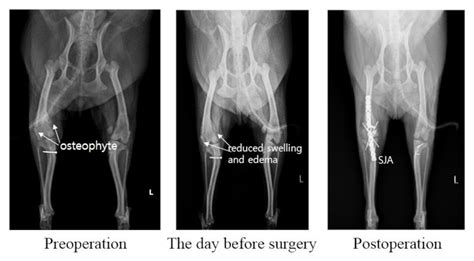

Stifle Joint Arthrodesis for Treating Chronic-Osteoarthritis-Affected Dogs